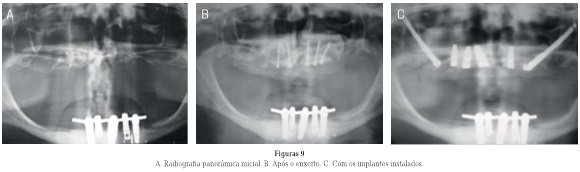

Enxertos ósseos de grande volume podem apresentar dificuldades quanto ao seu recobrimento cirúrgico, risco de exposição e manutenção do volume. Para minimizar os riscos e melhorar a previsibilidade, os autores idealizaram uma técnica de transplante de periósteo pediculado da calota craniana para recobrir enxertos ósseos maxilares extensos, e são apresentadas as bases teóricas sobre o procedimento. A técnica é apresentada em formato de caso clínico e consiste na abertura do escalpo do paciente, descolamento e transposição da gálea aponeurótica e periósteo para recobrir enxertos ósseos maxilares. Com 18 casos realizados e acompanhamento de 4-17 anos, a técnica se mostrou previsível e segura para casos de enxertos ósseos maxilares de grande volume.

Considerable bone grafts may present complications regarding its surgical risk of exposure and volume maintenance. To minimize risks and improve its predictability, the authors developed a technique to transplant pediculated periosteum of the skull to cover large maxillary bone grafts and present the theoretical basis of the procedure. The technique is presented in consecutive case reports and consists in opening the patient’s scalp, detachment and transposition of aponeurotic galea and periosteum to cover maxillary bone grafts. With 18 cases performed and 4-17 years of monitoring, the technique is predictable and safe in cases of maxillary bone grafts of large volume.